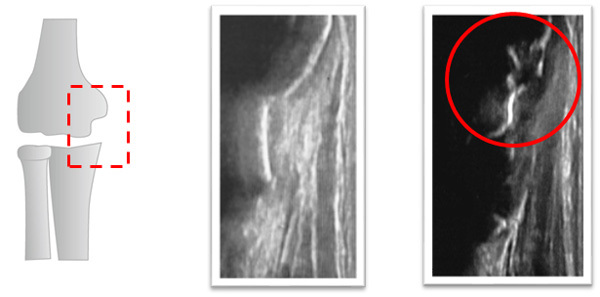

オスグットは脛骨粗面の部分が剥離骨折をするスポーツ傷害です。成長期の子供に多く起こります。

オスグットは成長期に治しておかないと膝の部分が突出してしまい、大人になっても運動をすると痛みが出てしまうようになってしまいます。

痛みが無くなったからといって運動を再開すると痛みが再発してしまいます。

エコー検査で経過観察をすることで、骨の修復の段階を確認でき、再発を防止することができます。